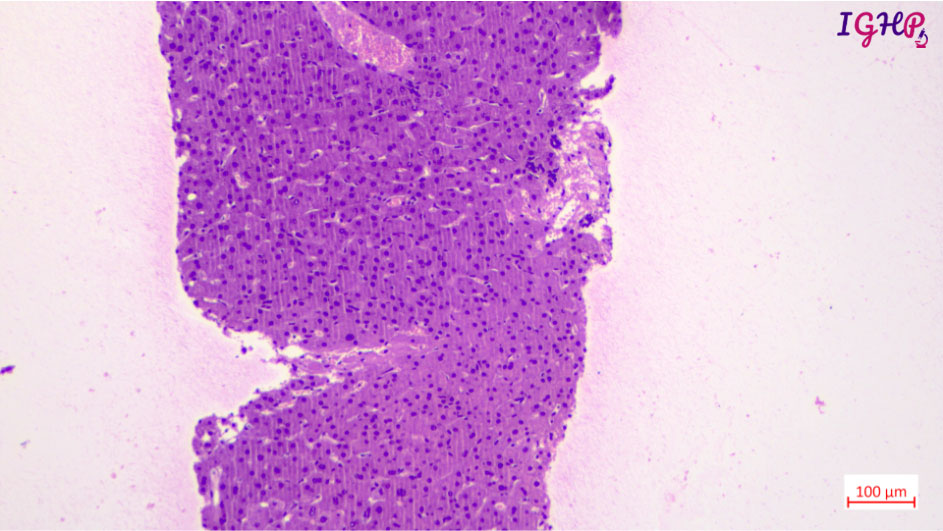

Microscopic Images-

Microscopic examination showed variable distortion of liver architecture with irregular distribution of portal tracts. At places the tracts appear atrophic with areas of close approximation. Few tracts showed absence of portal venous profiles and hypertrophied arterial vessels. There is presence of thin delicate blind ended fibrous septae around few of the portal tracts.

MT, Orcein and Reticulin stains performed showed maintained liver cell plate network with presence of thin delicate blind ended septae around few of the portal tracts.